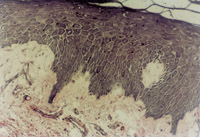

ԭλÇÐÈ¡´´Ãæ×éÖ¯²¡ÀíÇÐÆ¬¼ì²é£¬£¬ £¬£¬£¬£¬£¬£¬¼û»µËÀÉÏÆ¤×éÖ¯¼äÓдó×Ú¿ÅÁ£Ñù×éÖ¯£¬£¬ £¬£¬£¬£¬£¬£¬ÐÂÉúÉÏÆ¤Ï¸°ûºÍ½ºÔ­ÏËά×éÖ¯³ÊÍÅÑùÔöÉú£¬£¬ £¬£¬£¬£¬£¬£¬²¢¿É¼ûµ½µä·¶µÄÀàËÆÓÚÌ¥¶ùƤ·ô½á¹¹µÄƤ·ôÅßÌ¥»ù(embryonic base,EB)(ͼ5-3-4a,5-3-4b) ¡£¡£¡£¡£¡£¡£ ¡£¡£MEBTÖÎÁÆ10Ììºó£¬£¬ £¬£¬£¬£¬£¬£¬ÔÚ´´Ãæ±ßÑØÈ¡ÉÏÆ¤×éÖ¯²¡ÀíÇÐÆ¬¿É¼ûµ½½ÏԭʼµÄÉÏÆ¤×éÖ¯ ¡£¡£¡£¡£¡£¡£ ¡£¡£

5-3-4a ÐÂÉúÉÏÆ¤×éÖ¯ºÍ½ºÔ­ÏËάÔöÉú£¬£¬ £¬£¬£¬£¬£¬£¬¿É¼ûµä·¶EB£¨Æ¤·ôÅßÌ¥»ù£© HE¡Á40

5-3-4b ÐÂÉúÉÏÆ¤×éÖ¯Öпɼû΢Ѫ¹Ü£¬£¬ £¬£¬£¬£¬£¬£¬½ºÔ­ÏËάºÍÉÏÆ¤Ï¸°û(¸Éϸ°û)ÐÎ³ÉµÄÆ¤·ôÅßÌ¥»ù×éÖ¯  HE¡Á40